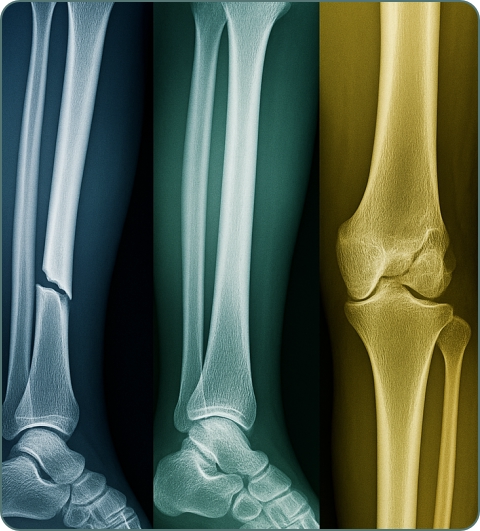

X-rays

First-line imaging for fractures, joint problems, and bone abnormalities. Quick, cost-effective, and excellent for detecting bone fractures and arthritis.